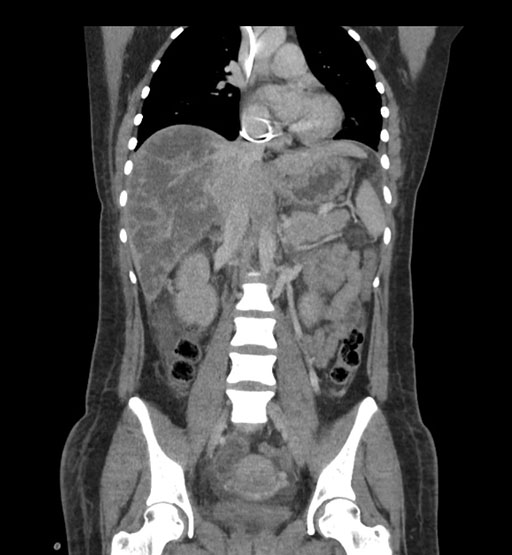

Coronal Arterial